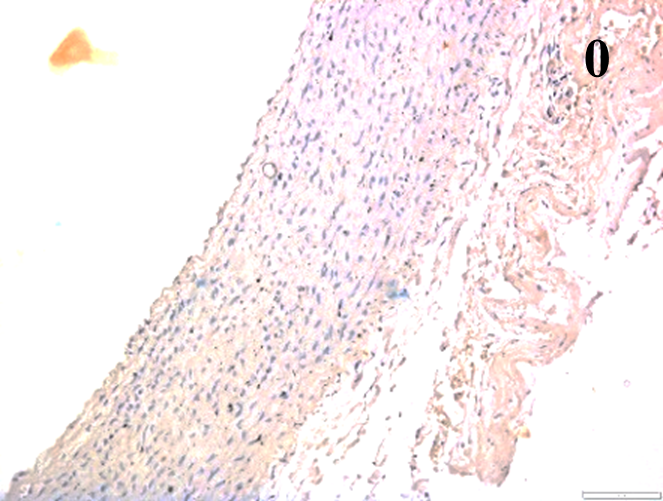

Immunoreactions of ICAM-1, VCAM-1, e-selectin, IL-6, IL-8, NF-

According to the percentage endothelial staining of cells, semi-quantitative

scores were applied. Score: 0 (negative); 1+ (1–10% positive cells); 2+

(11–25% positive cells) and 3+ (